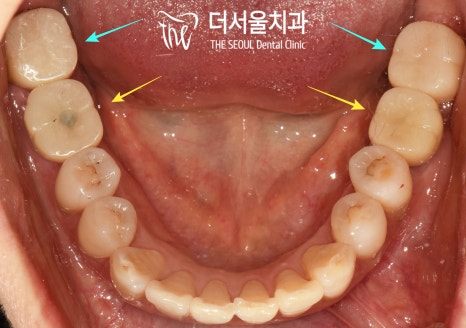

구강을 살펴보면

곳곳에

충치가 생긴 곳이 보이네요.

그런데 그중에서도

제가빨간색으로 표시해둔 부분은

우식의 깊이도 깊고 범위도 넓어서

빠른 해결이 필요한 상황이었습니다.

또한 노란색으로 표시해둔 부분은

뿌리가 부러진 채로

잇몸에 박혀있어서

발치를 하고 그 기능을 대체할

디지털 임플란트를 해주는 게

좋을 것으로 판단했습니다.

아랫니도 마찬가지인데요,

오른쪽 아래는 잔존 치근이 남아있고

왼쪽 아래는 이가 빠진지 시간이 오래되어

치조골의 폭이 좁아져있습니다.